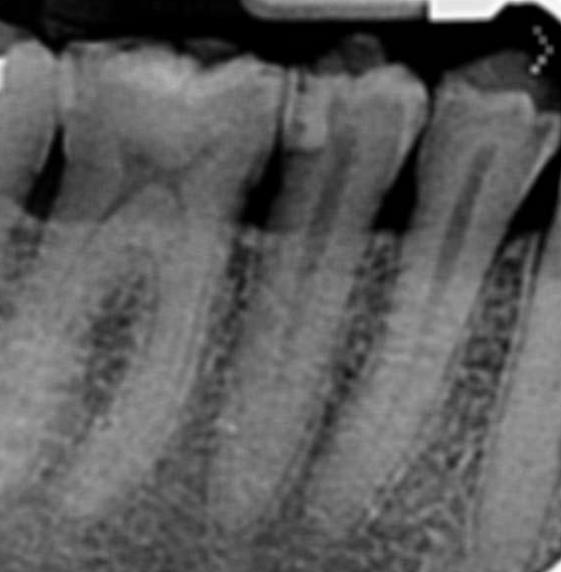

Salve.Io da un bel po di mesi ho continui dolori in zona molari superiori a sinistra.Ho effettuato almeno 20 visite dentistiche e 6 igienisti diversi mi hanno effettuato la detartrasi negli ultimi 2 anni.In una visita a Napoli un dottore mi ha fatto una rx endorale digitata ingrandita al pc e mi ha detto che tra questi 2 molari c’era tartaro calcificato da almeno 12 anni e mi ha inserito nel preventivo una carie sul secondo molare ma io tramite specchietto noto un buco nero anche sul dente del giudizio , inoltre mi ha detto che non e’ stata curata bene la carie sul premolare inferiore..Ho due carie anche se non e’ normale dopo tutte queste visite e detartrasi..Il radiologo mi ha inserito come referto questo : Piccole trasparenze smaltee interprossimali contrapposte 17-18 come per minute carie, reperti da accertare clinicamente.

Carie

sembra improbabile che i dolori di cui lei soffre siano riferibili alla parte superiore……il tartaro calcificato per esempio io non lo vedo, ne vedo particolari carie anche se devo fare i conti con una definizione non proprio ottimale delle immagine che mi ha mandato. Sinceramente proverei a riparare innanzitutto la vecchia otturazione che ha nell’arcata sottostante. Alle volte i dolori possono essere riferiti alle aree più impensate e poi rivalutarei la faccenda. Inoltre è anche probabile che quel dente la cui otturazione sarà da rifare, abbia un problema alla polpa infatti quella carie è molto profonda……. si faccia fare magari anche un test di vitalità per capire se ha bisogno di eseguire una cura canalare.

In sostanza prima di fare qualsiasi cosa nella parte superiore io agirei sotto.